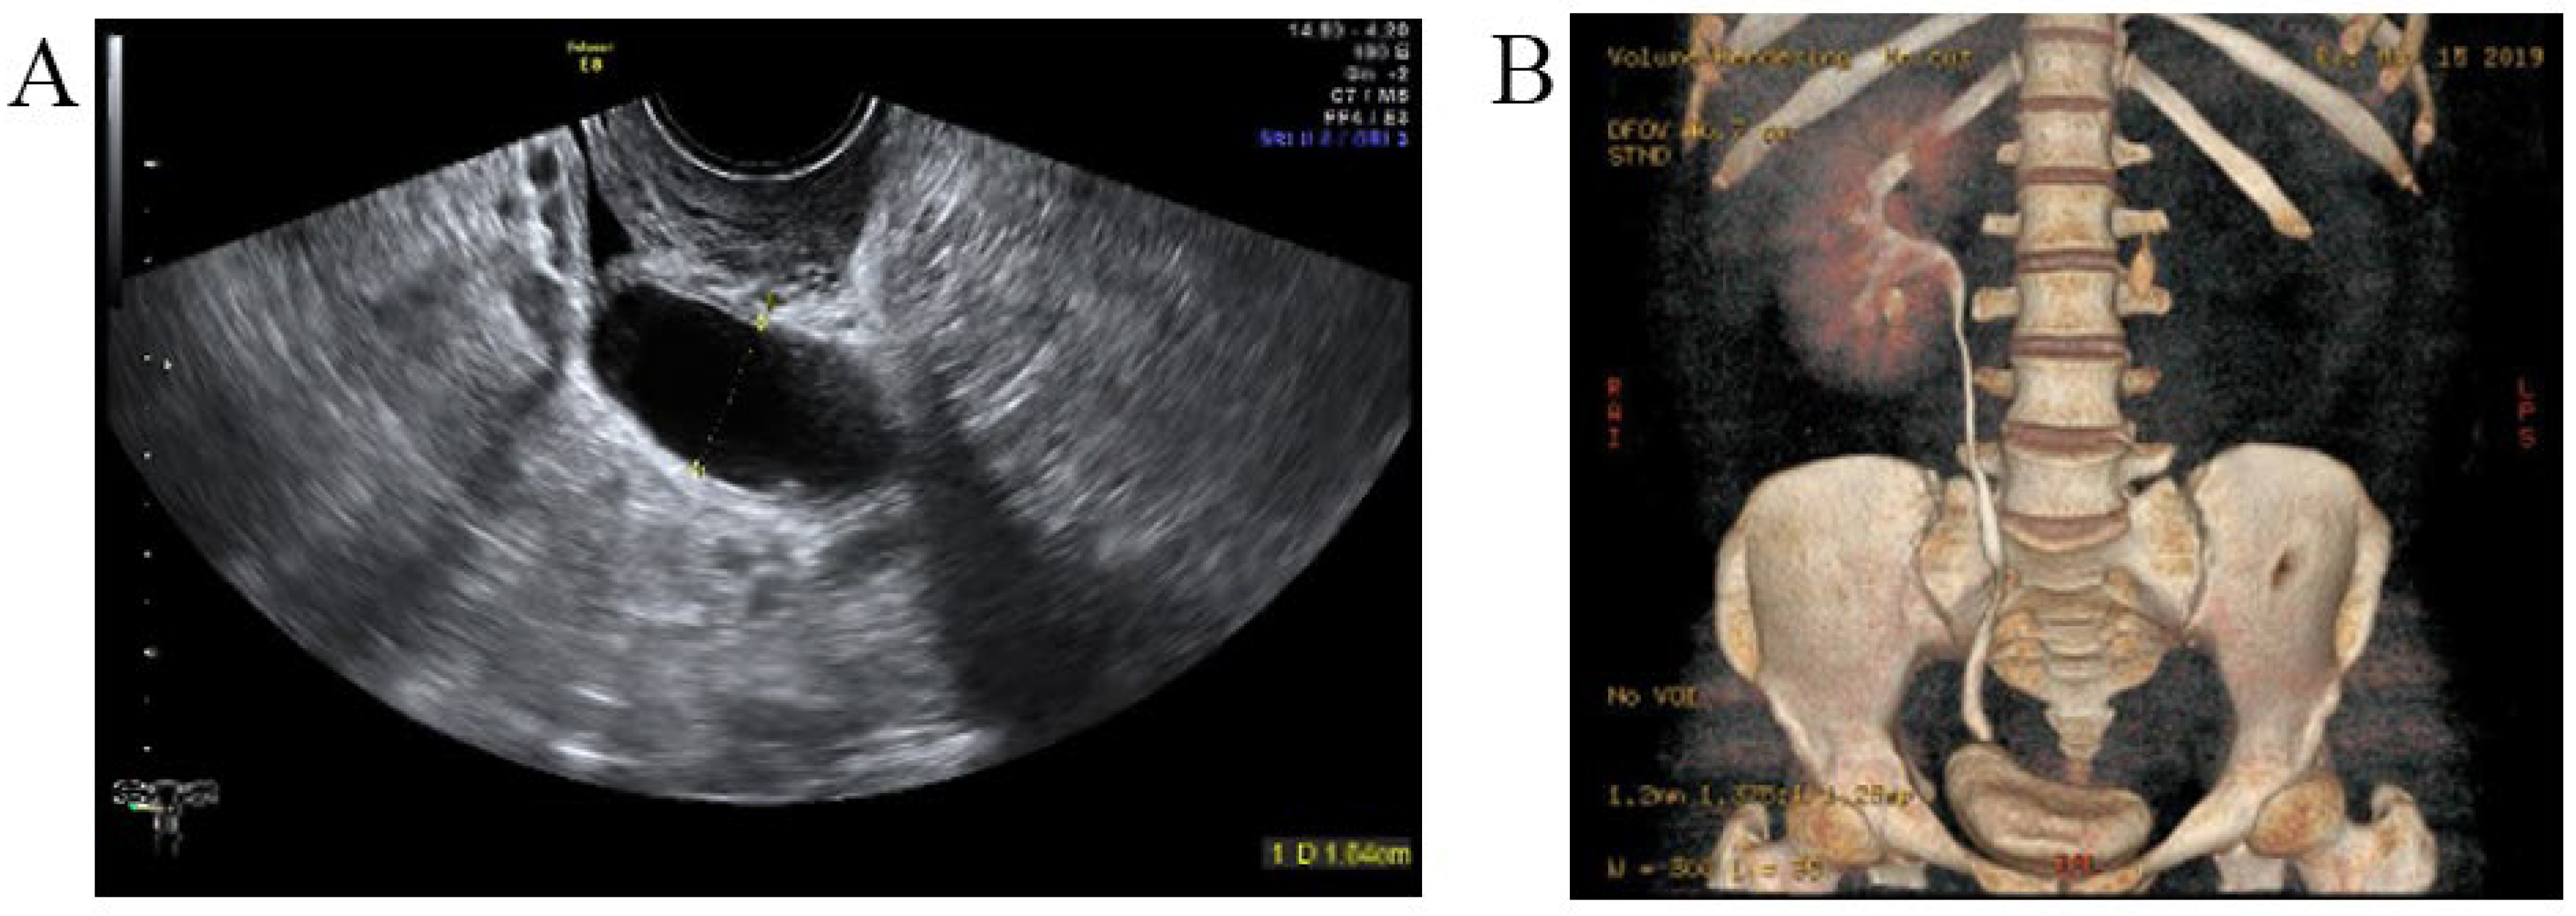

A 29-year-old woman was admitted to the hospital with complaints of urine incontinence since childhood and an ovarian cyst for three years. A urinary tract ultrasound demonstrated a right duplex kidney with an ectopic ureter and left kidney agenesis (Figure 9A). A CTU demonstrated a left ectopic ureter (Figure 9B). Because the patient had previously undergone a laparoscopic ovarian cystectomy for endometriosis and caesarean delivery, peritoneal adhesions potentially caused the laparoscopy to be challenging. Finally, the ovarian endometriosis cyst was removed, and the left ectopic ureter was reimplanted into the bladder via laparotomy.

Figure 9.

The left ectopic ureter. (A) Urinary tract ultrasound demonstrated that the ectopic ureter extended to the middle and upper parts of the vagina, and the widest diameter of this ureter (yellow arrow) was 1.6 cm. (B) The CTU demonstrated a left ectopic ureter.